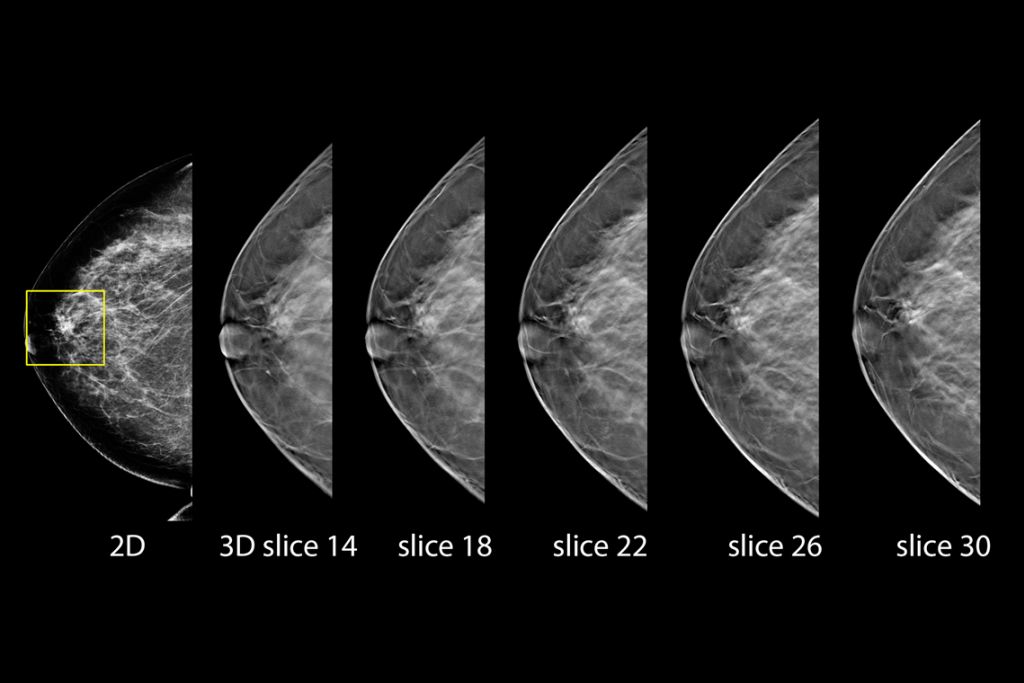

The 3Dimensions mammography system works with smart tomosynthesis technology, combining Clarity HD™ high resolution imaging, Intelligent 2D™ synthesised imaging and 3DQuorum™ SmartSlices for an efficient workflow.